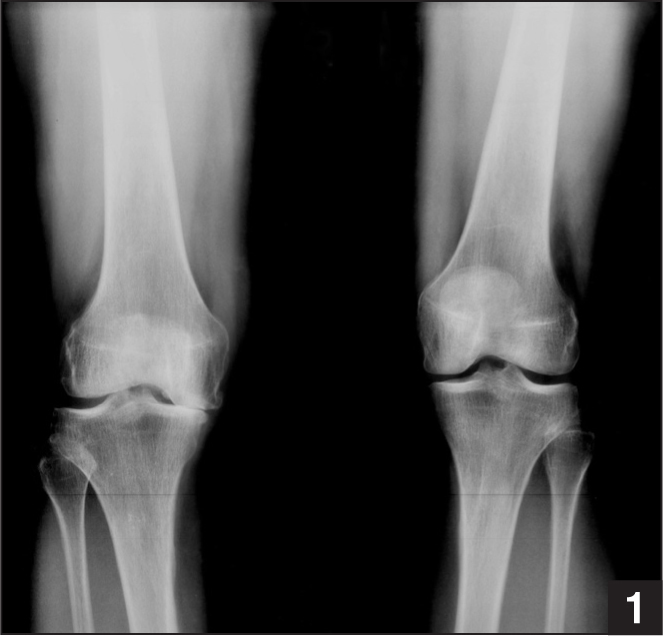

Options for this 65yo male with painful right knee?

Normal alignment of the knee

Lateral proximal femoral angle: 90 degrees

Mechanical Lateral distal femoral angle: 88 degrees

Anatomic Lateral distal femoral angle: 81 degrees

Medial proximal tibial angle: 87 degrees

Lateral distal tibial angle: 89 degrees

What is this depicting and what are your considerations when measuring the deformity?